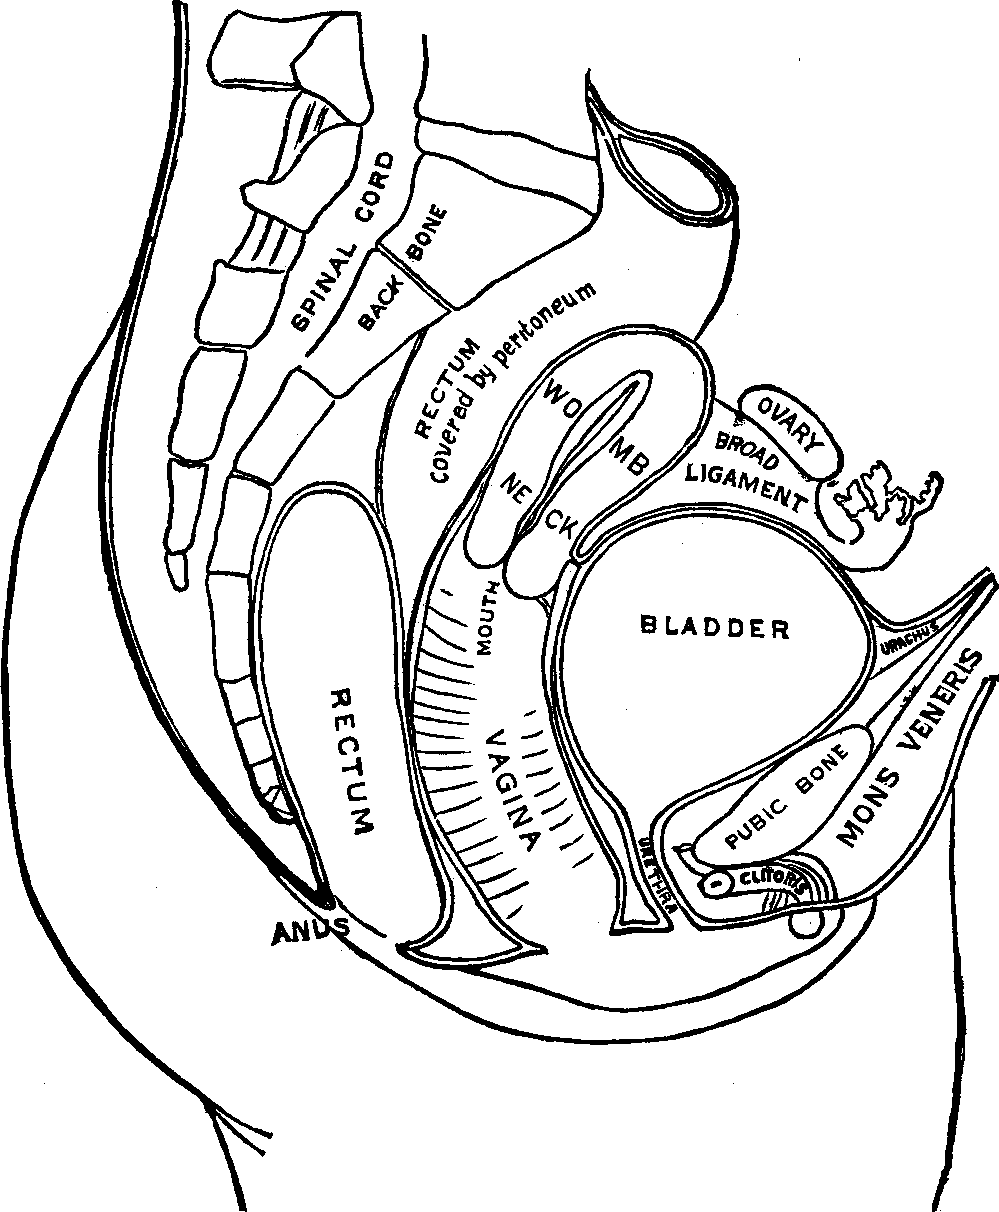

The Pelvis is an open bony structure, consisting of the Os Innominata, one on either side, and the Sacrum and Coccyx behind. The Sacrum, during childhood, consists of five bones, which in later years unite to form one bone. It is light and spongy in texture, and the upper surface articulates with the lowest vertebra, while it is united at its inferior margin to the coccyx. The Coccyx is the terminal bone of the spinal column. In infancy it is cartilaginous and composed of several pieces, but in the adult these unite and form one bone. The Innominata, or nameless bones, during youth, consist of three separate pieces on each side; but as age advances they coalesce and form one bone. A deep socket, called the acetabulum, is found near their junction, which serves for the reception of the head of the thigh-bone.

The Bones of the Lower Extremities, sixty in number, are classed as follows: The Femur, Patella, Tibia, Fibula, Tarsus, Metatarsus, and Phalanges. The Femur, or thigh-bone, is the longest bone in the body. It has a large round head, which is received into the acetabulum, thus affording a good illustration of a ball and socket joint. The Patella, or knee-pan, is the most complicated articulation of the body. It is of a round form, connects with the tibia by means of a strong ligament, and serves to protect the front of the joint, and to increase the leverage of the muscles attached to it, by causing them to act at a greater angle. The Tibia, or shin bone, is enlarged at each extremity and articulates with the femur above and the astragalus, the upper bone of the tarsus, below. The Fibula, the small bone of the leg, is situated on the outer side of the tibia, and is firmly bound to it at each extremity. The Tarsus, or instep, is composed of seven bones, and corresponds to the carpus of the upper extremities. The Metatarsus, the middle of the foot, bears a dose resemblance to the metacarpus, and consists of five bones situated between the tarsus and the phalanges. The tarsal and the metatarsal bones are so united as to give an arched appearance to the foot, thus imparting elasticity. The Phalanges, the toes, consist of fourteen bones, arranged in a manner similar to that of the fingers.